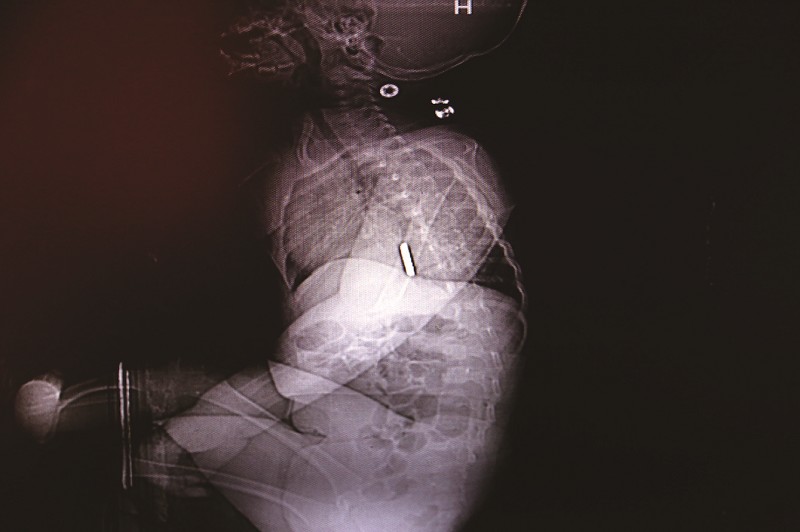

造影顯示,佳佳吞食的紐扣電池在食管下段。

“到太和醫(yī)院后,醫(yī)生為佳佳進行了胸部CT檢查,提示食管下段有異物,考慮為紐扣電池,且局部有縱膈膿腫。”昨日,太和醫(yī)院PICU副主任楊子江介紹,佳佳很快被收治在該院心胸外科,經(jīng)專家評估,因紐扣電池進入食管的時間較長,考慮食管穿孔的可能性較大,需及時開展手術(shù)。